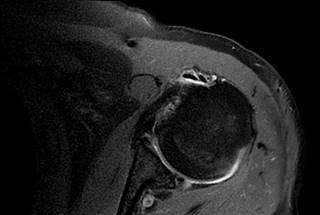

Figura 2: Resonancia magnética de hombro izquierdo en adquisición axial T2 con saturación grasa en la que se observan dos imágenes hipointensas a nivel de la corredera bicipital en probable relación a duplicación de la porción larga del bíceps asociado a incremento en el líquido sinovial en este sitio.

Cuando se habla de duplicidad de tendón largo del músculo bíceps braquial se observará un fascículo menor proveniente de la superficie del músculo supraespinoso y otro fascículo que proviene de la porción anterosuperior del labrum, ambos fascículos retoman el curso de la corredera bicipital (Figura 2). En el caso del paciente que se presenta, se asocia a tendonitis de la porción larga, lo que facilita la identificación de ambos fascículos por el líquido sinovial que rodea dichas estructuras.4